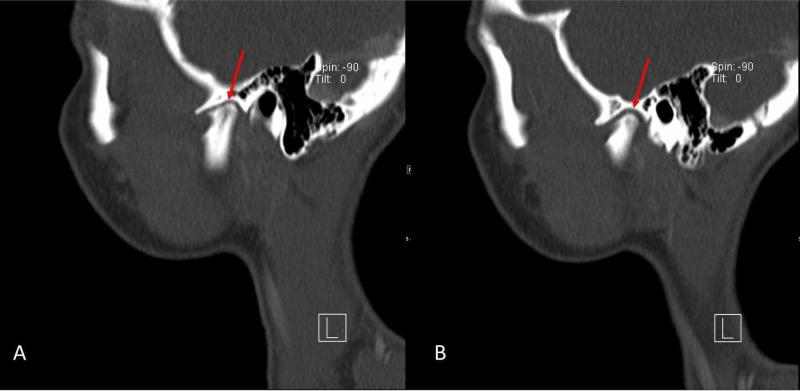

Idiopathic mandibular condylar resorption is a rare condition in which the mandibular condyle of the temporomandibular joint (TMJ) becomes resorbed and thus reduces in size and volume. This leads to TMJ dysfunction that commonly requires surgical correction; however, more conservative interventions can also be utilized. We present a case of idiopathic mandibular condyle resorption in a 17-year-old female presenting with TMJ pain and clicking with mastication. A definitive diagnosis of this condition ultimately requires imaging studies, a reliable option being magnetic resonance imaging (MRI), which will reveal erosion of the mandibular condylar process (often bilaterally) with diminished mass and volume leading to the known sequelae of symptoms.

特发性下颌髁突吸收是一种罕见的病症,其中颞下颌关节(TMJ)的下颌髁突会被吸收,从而尺寸和体积减小。这会导致颞下颌关节功能障碍,通常需要手术矫正;然而,也可以采用更保守的干预措施。我们报告一例17岁女性特发性下颌髁突吸收病例,该患者表现为颞下颌关节疼痛以及咀嚼时弹响。对这种病症的明确诊断最终需要影像学检查,可靠的选择是磁共振成像(MRI),它将显示下颌髁突的侵蚀(通常为双侧),伴有质量和体积减小,进而导致已知的一系列症状。